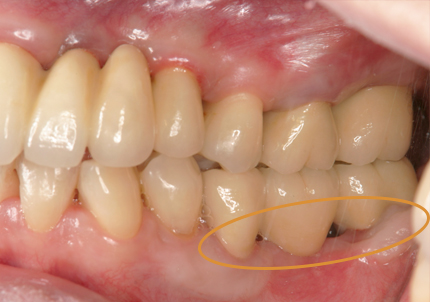

1.初診時口腔内(2007年6月30日)

8.初診より現在に至る

強い歯ぎしり、くいしばりで奥歯の歯牙破折、深い虫歯で保存不可能となり全顎治療となる。

↑ 2025年9月9日

治療後は経過良好